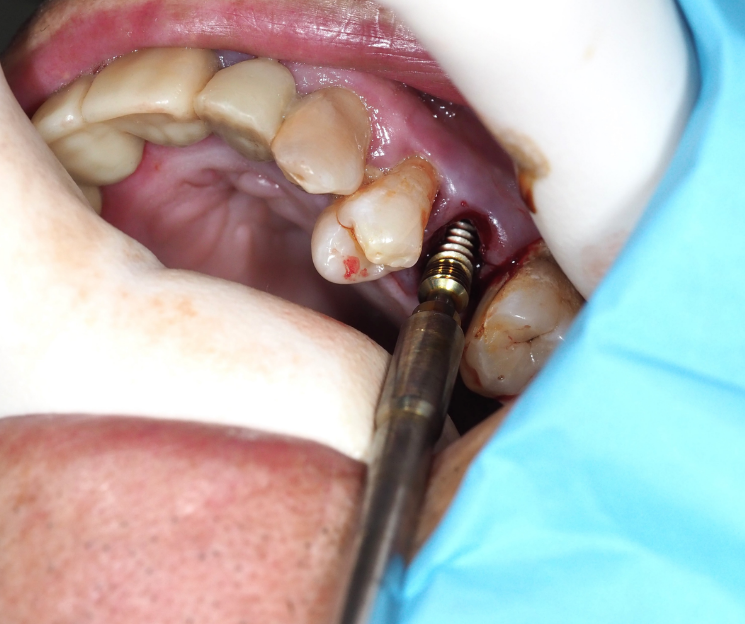

- Colocación del implante: Se procedió a la inserción del implante monofásico compresivo en el mismo acto quirúrgico.

- Estabilidad: Gracias a la condensación ósea lograda, se obtuvo una fijación óptima que permitió la carga inmediata.

- Ventaja de los implantes compresivos: Son ideales para huesos esponjosos o de baja densidad, ya que transforman el lecho receptor aumentando su densidad, facilitando la carga inmediata y acortando los tiempos de tratamiento.